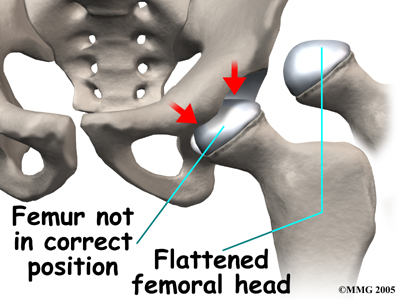

Whatever the true cause of ischemia (lack of blood to the area), the result is bone death (called necrosis) of the femoral head. Without a normal blood supply, the bone loses its strength and shape. The loss of bone density and softening of the head result in a femoral head that is misshaped. With the hip supporting the weight of the body, tiny microfractures in the soft, necrotic bone fail to heal. This is another reason why normal wear and tear results in a deformity.

The main problem with Perthes disease is that it changes the structure of the hip joint. How much it affects the way the hip joint works depends on how much the hip joint is deformed. Muscle weakness and atrophy affecting the thigh and calf muscles may develop over time. The affected leg can shorten as a result of the changes in the hip. The result may be a significant leg length difference. Problems later in life are more likely the greater the deformity after the condition has healed.

The main problem with Perthes disease is that it changes the structure of the hip joint. How much it affects the way the hip joint works depends on how much the hip joint is deformed. Muscle weakness and atrophy affecting the thigh and calf muscles may develop over time. The affected leg can shorten as a result of the changes in the hip. The result may be a significant leg length difference. Problems later in life are more likely the greater the deformity after the condition has healed.

The primary goal of treatment for Perthes disease is to help the femoral head recover and grow to a normal shape. The closer to normal the femoral head is when growth stops, the better the hip will function in later life. The way that surgeons achieve this goal is using a concept called containment.